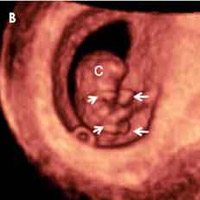

El embrión mide entre 2 y 3 centímetros en la semana 9 de embarazo y su forma ya es mucho más parecida a un ser humano:

Aparecen las manos con los dedos y las muñecas, que se sitúan a la altura del corazón.

Las piernas se alargan, se dirigen a la línea media del cuerpo y en ellas aparecen los pies con sus dedos correspondientes.

La cabeza sigue siendo la parte más grande en proporción con el resto del cuerpo. La cabeza vez está más erecta y con forma redondeada.

En la cara, lo párpados cubren parcialmente los ojos. Los pabellones auriculares están bien formados. La boca se aprecia e incluso se abre.

La ecografía de la semana 9 de embarazo

En la ecografía de la semana 9 puedes ver cómo el embrión se contornea moviendo el cuerpo y los miembros superiores e inferiores. Todavía es pronto para determinar el sexo por ecografía, ya que aún no se han formado los genitales.